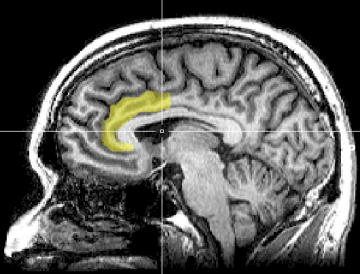

Prefrontal cortex.

Hypnosis modulates activity in the brain areas involved in the regulation of consciousness.

PET scans of cerebral blood flow in hypnosis show the involvement of the anterior cingulate cortex (ACC), the thalamus, and the ponto-mesencephalic brainstem. Hypnosis increases blood flow in the occipital region, which is consistent with the theory that hypnosis decreases cortical arousal (i.e., cortical inhibition theory). Increases in mental absorption during hypnosis were associated with increased blood flow in the brain's attentional system.[4]

Anterior cingulate cortex (ACC).